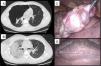

Our patient was a 28-year-old man, who, after a 5-day history of pleuritic pain, was diagnosed with complete right pneumothorax on chest CT. After insertion of a 10F pleural drainage tube connected to −20cm H2O suction the patient developed irritative cough, central chest pain, hypotension, tachycardia, and desaturation. He was stabilized in the ICU, and a repeat CT scan was requested, showing ground glass opacities in the right lung, consistent with reexpansion pulmonary edema (Fig. 1). The patient did not improve and required invasive mechanical ventilation. Extubation was achieved after 48h. Apical bullous lesions and multiple blebs were observed during surgery for bullectomy and mechanical pleurodesis by video-assisted thoracoscopy. The pleural drainage tube was removed and the patient was discharged 72h after surgery, without complications.

Reexpansion pulmonary edema, first described in 1853 by Pinault, is a rare complication, usually less than 1%, that occurs after rapid reinflation of the lung following evacuation of a pneumothorax or pleural effusion. Mortality can be as high as 20%.1 Diagnosis is clinical, supported by imaging tests. Treatment is based on supportive measures, requiring CPAP or even IMV with PEEP in the most severe cases, as occurred in our patient. Clinical suspicion is fundamental to guiding diligent action.2